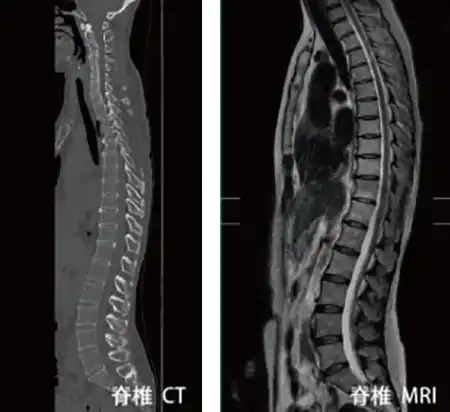

| CT(コンピューター断層撮影) | 骨病変以外の椎間板、神経の状態をチェックするのに必須検査です。椎間板へルニア、腫瘍、のう腫病変、脊髄の変性、髄内病変の有無などがわかります。 |

| MRI(磁気共鳴断層撮影) | 骨病変以外の椎間板、神経の状態をチェックするのに必須検査です。椎間板ヘルニア、腫瘍、のう腫病変、脊髄の変性、髄内病変の有無などがわかります。 |